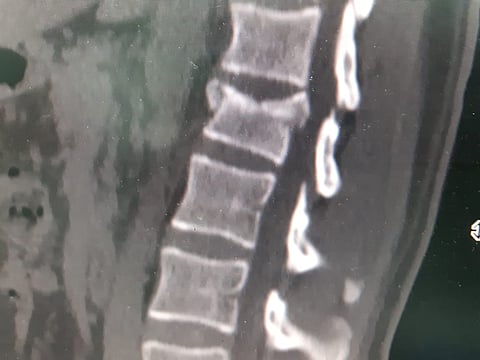

نجح فريق طبي بقسم المخ والأعصاب بمستشفى طريف العام، في إجراء عملية معقدة لمصاب في حادث مروري نتج عنه كسر مفتت في الفقرة القطنية الأولى، تسبّب له بضعف في الحركة والأطراف السفلية.

وقرّر الفريق المكوّن بقيادة الدكتور الاستشاري محمد الحاج، وقسم العظام الاستشاري عادل عبدالغني، والدكتور غانم حمدي، وطاقم التخدير بقيادة الدكتور محمد جمال، والممرضة حنان العنزي، بعد استكمال الإجراءات الطبية اللازمة لمثل تلك الحالات، إجراء عملية متقدمة للمريض تمكّن من خلالها الأطباء، بفضل الله، من إجراء خزع قوس الفقرة المكسورة وتحرير الجذور العصبية والسحايا، ثم تثبيتها مع فقرة فوقها وفقرة تحتها أيّ مع الظهرية الثانية عشرة والقطنية الثانية بوساطة ٤ براغي وقضيبين من التيتانيوم.

وأوضح مدير القطاع الصحي والمشرف على مستشفى طريف العام فايز سرحان الرويلي؛ أن الفحوص الإشعاعية أظهرت وجود كسر في الفقرات القطنية المتقدمة للمريض، وتمّ إجراء العملية لكي تتم إزالة الضغط على الحبل الشوكي وتثبيت الفقرات القطنية بمسامير وصفائح طبية، وذلك في إجراءٍ طبي أسهم في تحسُّن حركة الأطراف السفلى للمريض، واستعادة قدرته على المشي وتكللت العملية بالنجاح التام، ولله الحمد.